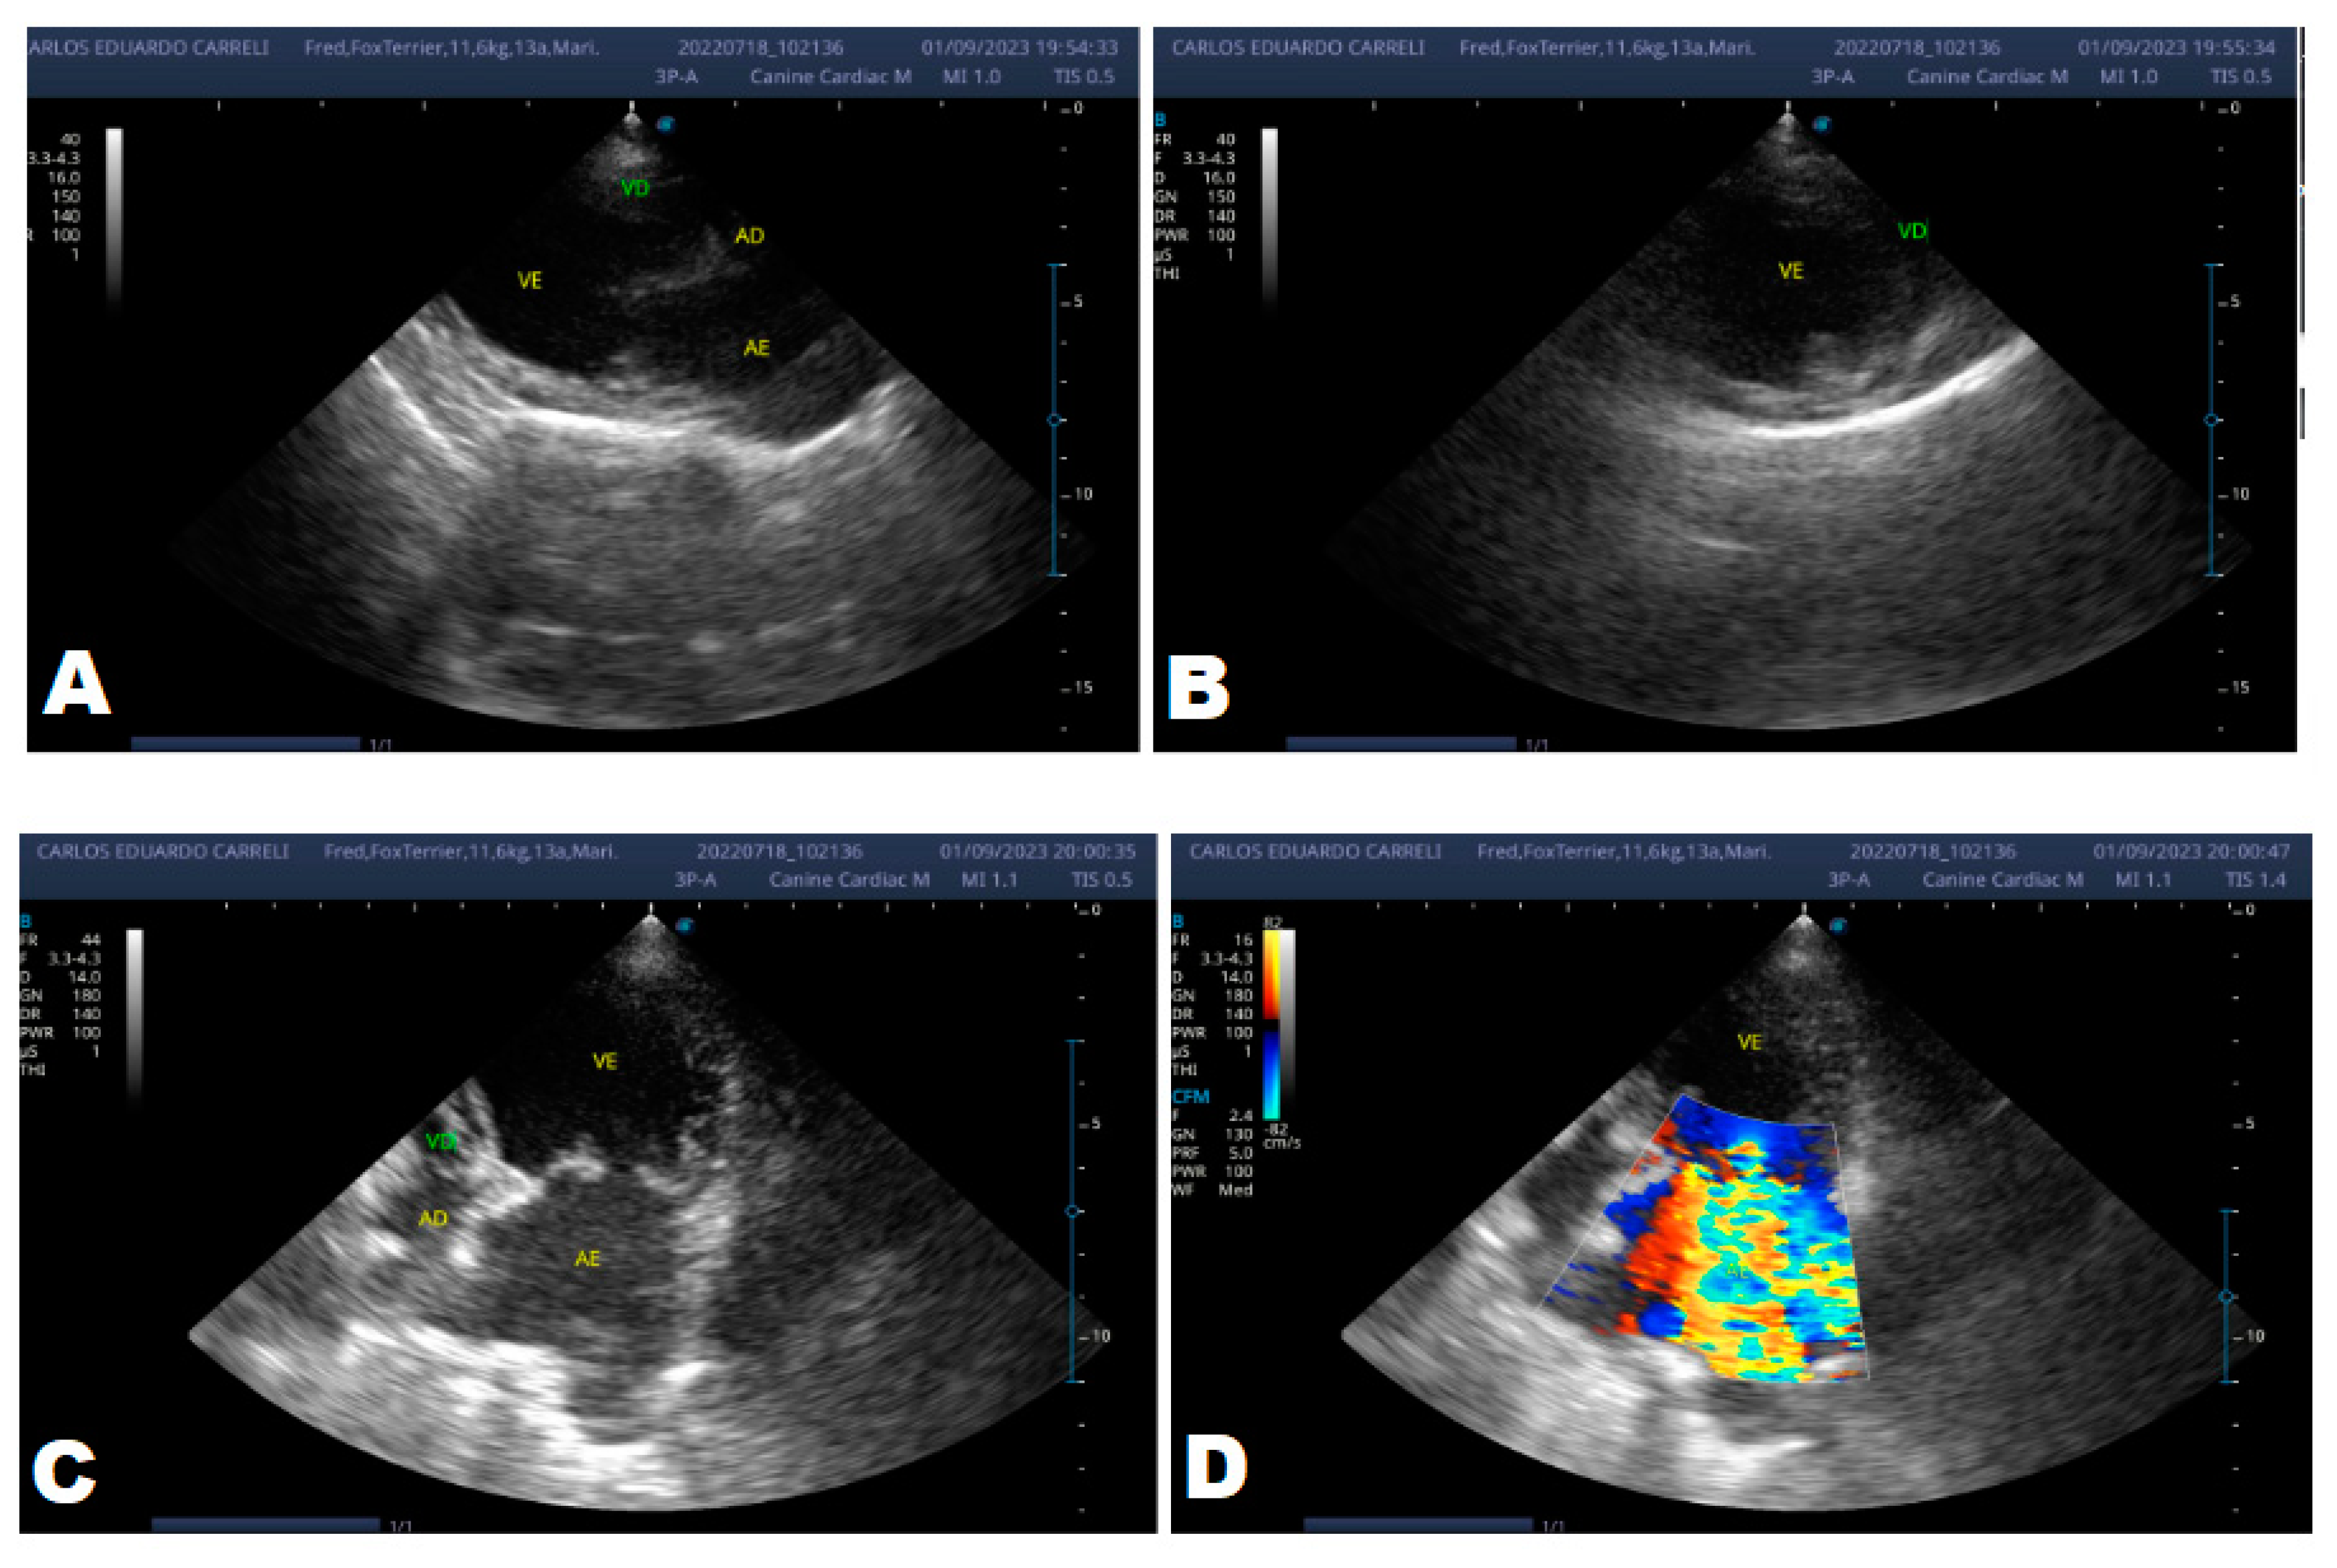

After eight months, the patient returned with a worsening condition, repeated ECHO (Figure 6) and ECG (Figure 7) where diastolic dysfunction and worsening of the arrhythmia were observed. Amiodarone 8.7 mg/kg orally was prescribed, replacing sotalol, 1 tablet BID, and in addition, Furosemide (Lasix) 1.7 mg/kg orally was prescribed every 12 hours. Pimobendan was continued. After a week, a reassessment was carried out and the ECG demonstrated stability in the arrhythmia (Figure 8).

In the same year, eight months later, the patient returned with a worsening condition, presenting pulmonary edema. With these changes, the animal's condition progressed to stage C, requiring repeat echocardiographic and electrocardiographic examinations.

The ECHO (Figure 6) showed an increase in the cardiac chambers as well as diastolic dysfunction when compared to the previous exam. The ECG (Figure 7) revealed polymorphic premature ventricular extrasystoles. Due to this change, sotalol was replaced by amiodarone.

Figure 6. Echocardiogram (September/2023): significant enlargement of the left heart chambers observed; observed in a Doppler study, systolic turbulent flow within the left atrium characterizing significant mitral valve insufficiency; Observed left ventricular diastolic dimension above normal limits, with normal systolic function parameters, characterizing systolic dysfunction; A left ventricular filling pattern of the E>A wave type and an increased E/A ratio were observed, characterizing diastolic dysfunction (restrictive or pseudo-restrictive pattern).